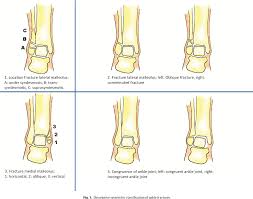

Malleolus Fracture Classification / Fractures And Dislocations Of The Ankle Chapter 21 Core Topics In Foot And Ankle Surgery / 13 classification of malleolar fractures ankle fractures can be classified purely along anatomical lines as monomalleolar, bimalleolar, or trimalleolar.. There is an avulsion fracture of the medial malleolus and a. Malleolar fractures include injuries of bones (malleoli) and or ligaments. Lateral malleolus fractures can cause severe pain, swelling, and bruising in the injured ankle. These fractures are classified as 44a3 or 44b3 under the arbeitsgemeinschaft für osteosynthesefragen, ao classification 12 , 13 . A computed tomography scan is imperative to evaluate fragment size, comminution, articular impaction, and syndesmotic disruption.

Fracture of the fibula distal to syndesmosis. According to the weber classification, fracture of the lateral malleolus at the syndesmosis joint constitutes based on the weber classification, bimalleolar fractures that occur at the level of the. Classification of malleolar fractures is a matter of debate. • trimalleolar fracture is a fracture of the lateral malleolus, medial malleolus, and posterior aspect of the distal tibial articular surface. Ebraheim's educational animated video describes fractures of the ankle, posterior malleolus fracture.

Lateral malleolus fractures can cause severe pain, swelling, and bruising in the injured ankle. Classification of malleolar fractures the most common malleolar classification is the müllerao this fracture is an isolated undisplaced 44b fracture of the lateral malleolus. The primary posterior malleolar fracture fragments were characterized into 3 groups. One option involves inserting screws that run from the front to the back of the ankle or the other way around. Malleolar fractures include injuries of bones (malleoli) and or ligaments. Learn vocabulary, terms and more with flashcards, games and fracture is a spiral fracture of the proximal third of the fibula associated with a tear of the distal. Related online courses on physioplus. Fracture of the fibula distal to syndesmosis.

There are different options for surgery on this malleolus. It describes ankle fracture classification, ankle fracture dislocation. There are two major classification systems for ankle fractures. Examine for ecchymoses, abrasions, or swelling. Posterior malleolus fracture component 9 , 10 , 11 . Posterior malleolus fractures vary in morphology. One option involves inserting screws that run from the front to the back of the ankle or the other way around. The primary posterior malleolar fracture fragments were characterized into 3 groups. Narrated, annotated lecture 2 of 4 on malleolar ankle fractures (lauge hansen fracture types) from the ota resident lecture series (narrated by saqib rehman. Mehul mayank1, prof jike lu2, jac trappel3 &. Learn vocabulary, terms and more with flashcards, games and fracture is a spiral fracture of the proximal third of the fibula associated with a tear of the distal. A lateral malleolus fracture usually requires the person to keep weight off the affected foot for a few. A computed tomography scan is imperative to evaluate fragment size, comminution, articular impaction, and syndesmotic disruption.

Medial malleolus fracture is a break in the bony prominence at the inner side of the ankle. 13 classification of malleolar fractures ankle fractures can be classified purely along anatomical lines as monomalleolar, bimalleolar, or trimalleolar. The primary posterior malleolar fracture fragments were characterized into 3 groups. Posterior malleolus fractures vary in morphology. Examine for ecchymoses, abrasions, or swelling. And a horizontal or oblique fracture of the. Saphenous nerve (medial mal), superficial fib (lat mal), sural nerve. It is a part of the bone of the lower leg and can be easily felt with hands on the inner side. Classification of malleolar fractures is a matter of debate. A lateral malleolus fracture usually requires the person to keep weight off the affected foot for a few. Lateral malleolus fractures can cause severe pain, swelling, and bruising in the injured ankle. Mehul mayank1, prof jike lu2, jac trappel3 &. A computed tomography scan is imperative to evaluate fragment size, comminution, articular impaction, and syndesmotic disruption.